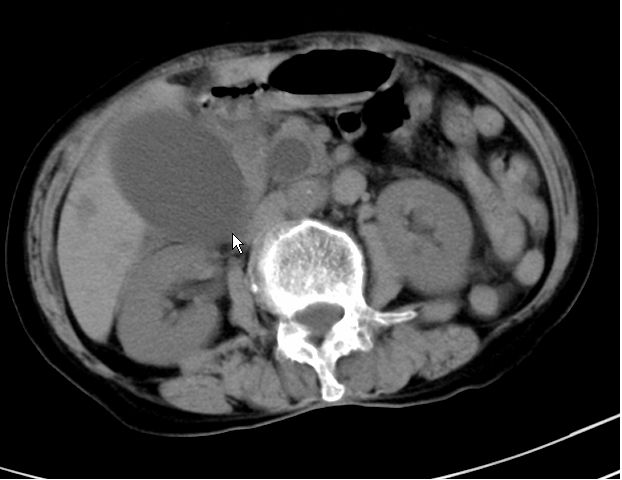

以下是引用zjzjr在2008-12-16 12:49:00的发言:[br]肝内外胆管全程扩张,胆囊明显增大,未见占位征像.建议mrcp.

以下是引用jiangjing在2008-12-16 13:19:00的发言:[br]肝内外胆管全程扩张,胆囊明显增大,扩张胆总管下段径较中上段小,未见胰管扩张,提示胆总管远端梗阻伴感染.建议增强及mrcp 检查

以下是引用朱亮在2008-12-16 12:54:00的发言:[br]胆总管远端应薄层扫描 胆总管逐渐变细 考虑胆系慢性炎症